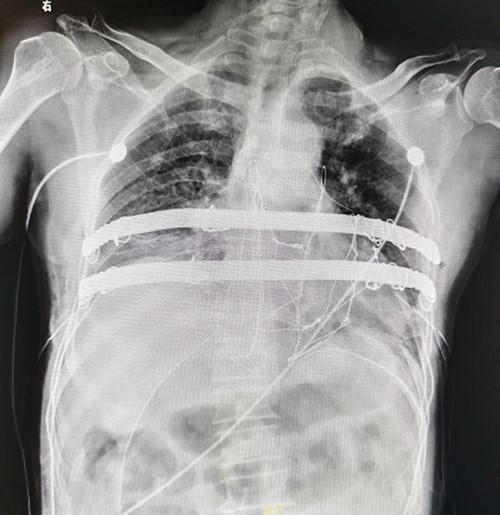

The patient is a 65-year-old male. He was found to have a mass in the middle of the chest wall 1 year ago, without any discomfort. In the past 2 months, the mass grew rapidly with local pain. The patient was recently admitted to our hospital for surgery. Preoperative physical examination showed that there was a mass in the middle of the anterior chest wall, about 5 × 5 cm in size, with obvious tenderness and unclear boundary (Fig. 1). Imaging examination revealed a sternal tumor, which was located in the sternal body and invaded the surrounding costal cartilages (Fig. 2). The operation was performed under general anesthesia. In supine position, a longitudinal incision was made in the middle of the anterior chest wall to expose the tumor, and the tumor was removed along the periphery. The resection location was ~3 cm away from the border of tumor. After resection, a huge defect was formed in the middle of the anterior chest wall. Incisions were made on the lateral chest wall to expose the surrounding ribs. Wenlin procedure was performed with two steel bars [6, 7]. The curvature of the bar was the normal curvature of the chest wall. Both ends of the bar were firmly fixed with two adjacent ribs [8]. A mesh was woven between the two steel bars and the upper and lower ribs with steel wires, and the inner and outer sides of the steel bars were padded and fixed with fiber membranes. Drainage tubes were placed in both thoracic cavities and surgical fields (Fig. 3). After the incisions were closed, the operation was completed (Fig. 4). The operation time was 95 min, the intraoperative bleeding was 30 ml, and no complications occurred during the operation. The patient recovered smoothly after operation. Postoperative X-ray examination showed that the positions of the steel bars were normal (Fig. 5). He was discharged 10 days after operation.